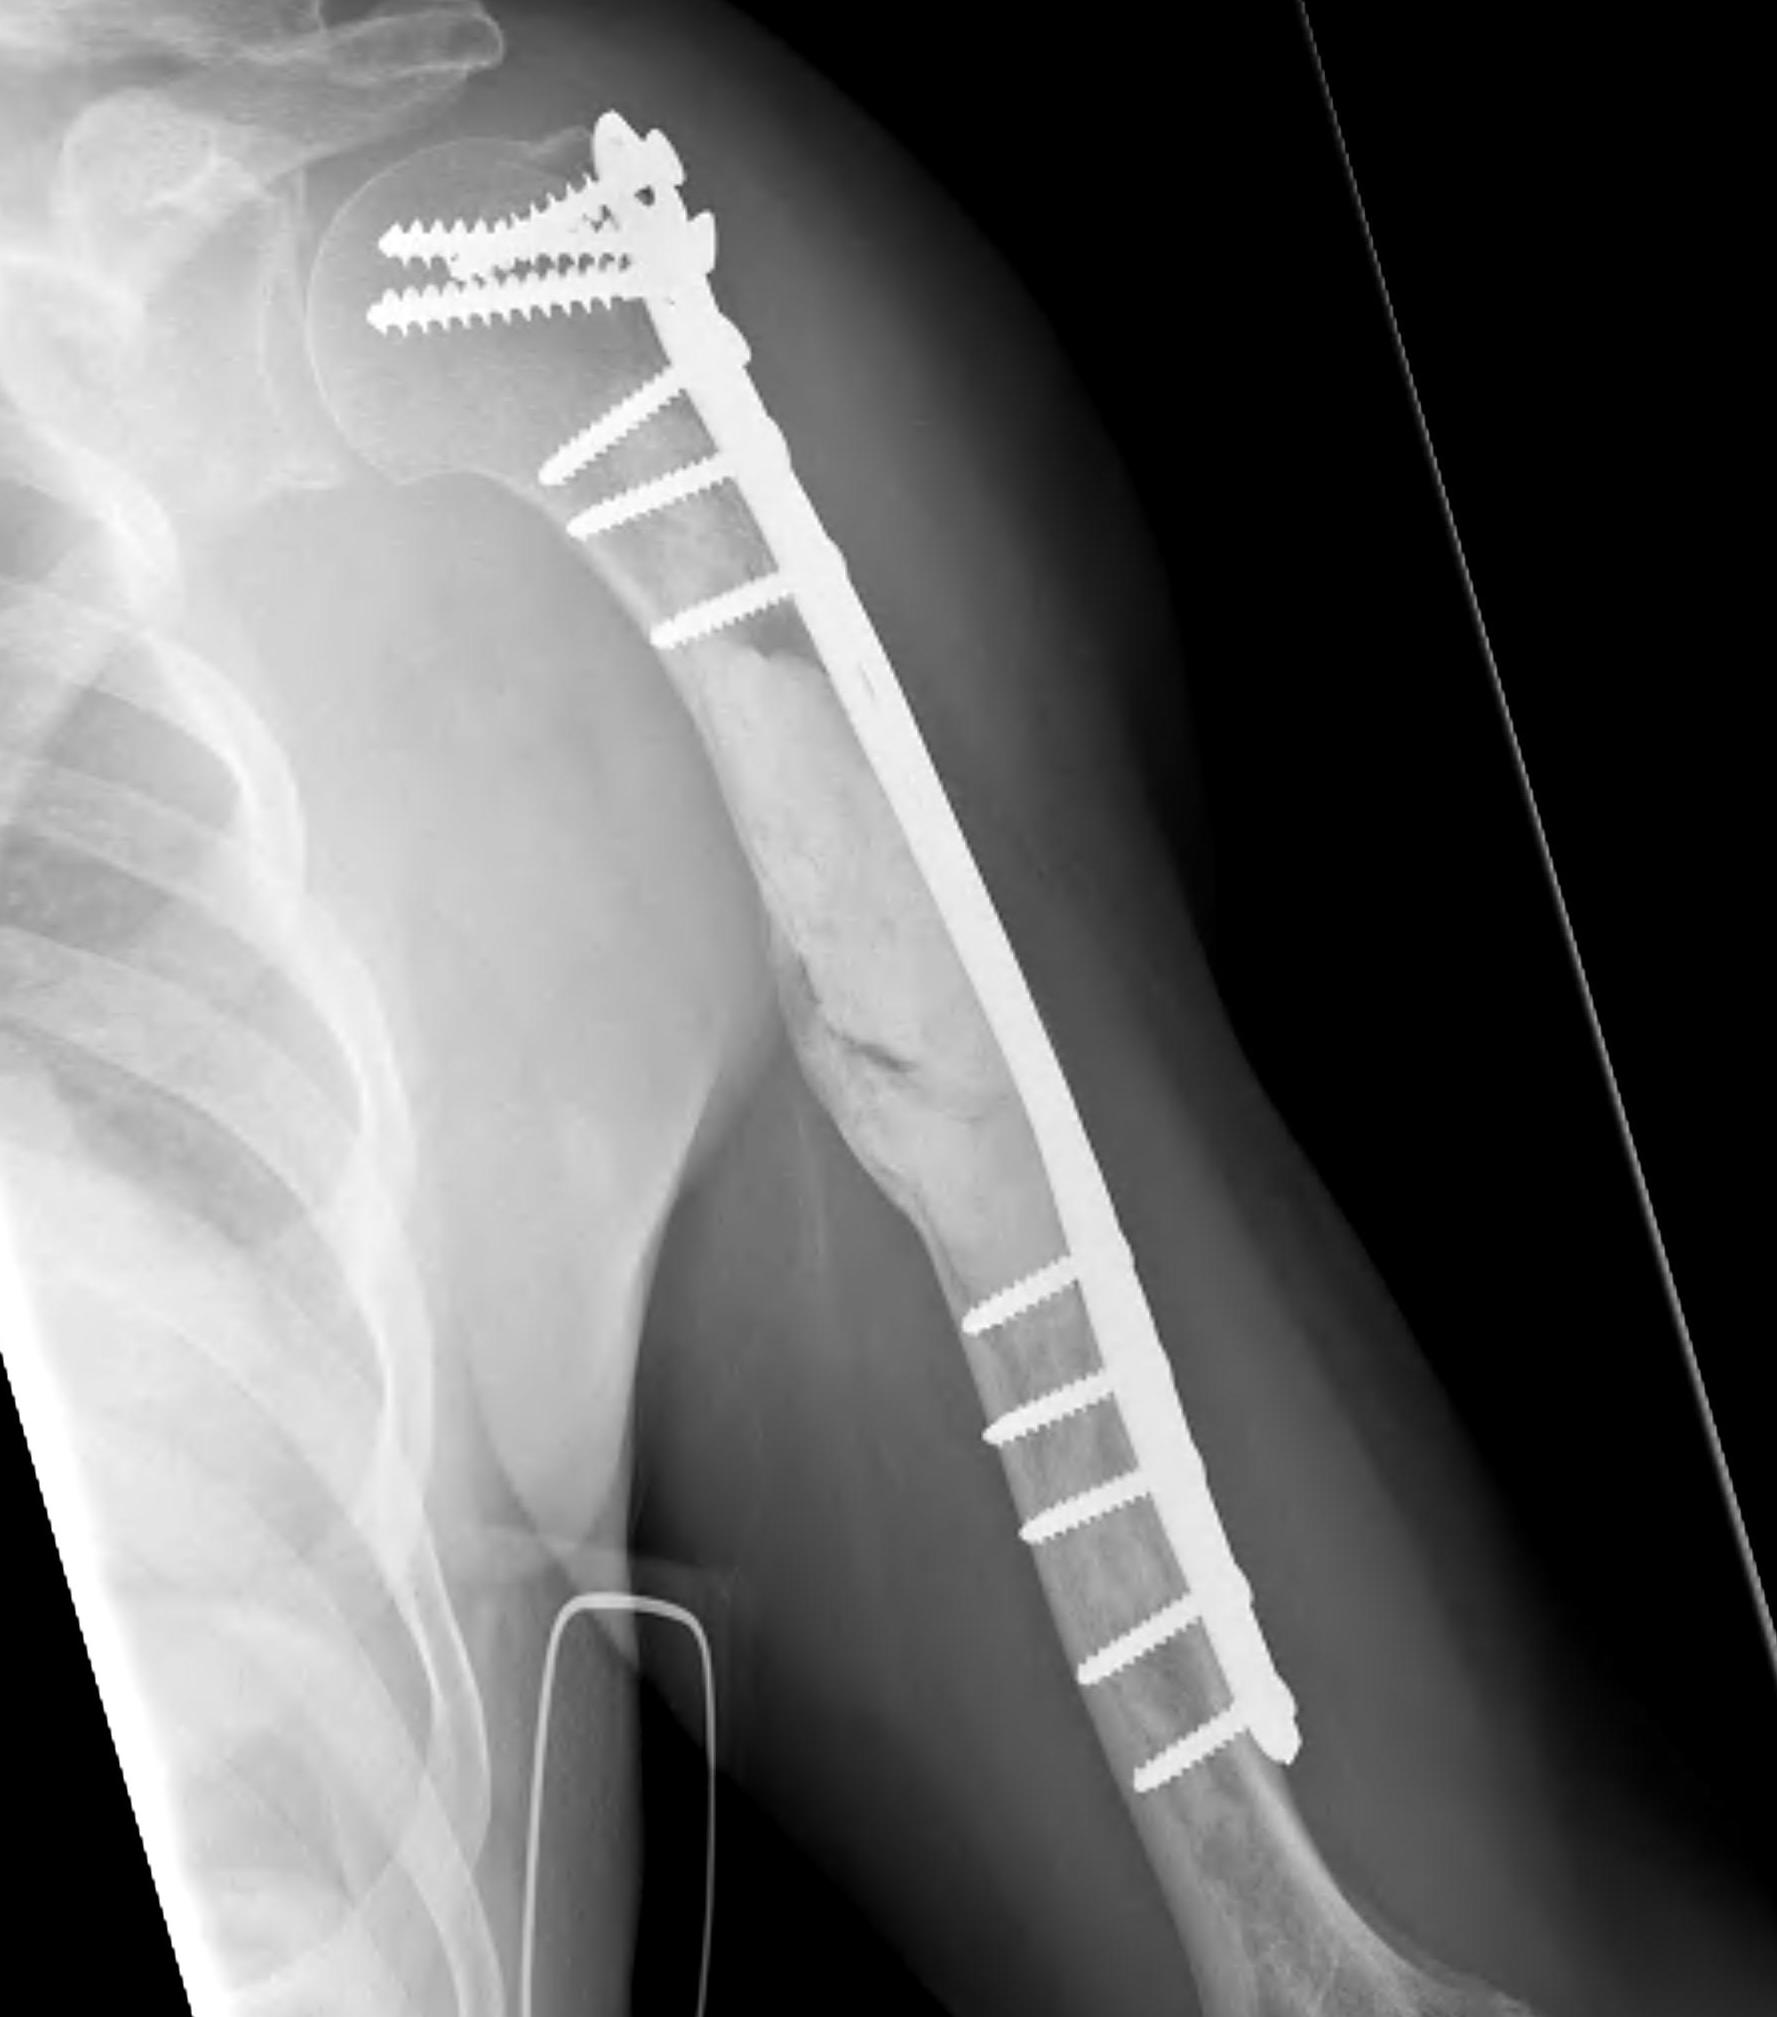

Proximal Humerus

Options

ORIF with plate +/- cement

IMN +/- cement

Tumour prosthesis

Results

Wu et al J Orthop Traumatol 2023

- 45 patients with proximal humerus metastasis

- IM nailing + cement versus plate

- lower blood loss and shorted hospital stay with IMN

- better pain relief with IMN